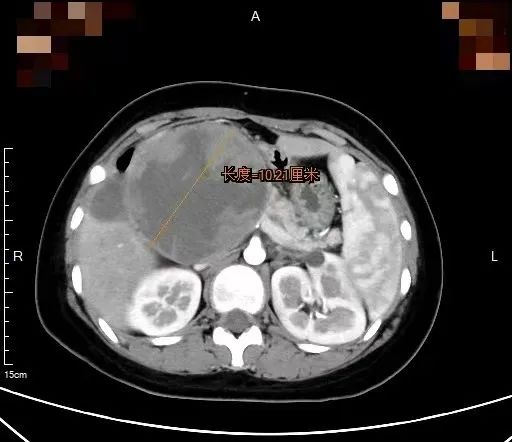

增强CT检查显示,一个直径10厘米的肿瘤像狰狞的章鱼,触须般的包膜紧紧缠绕着小微的胰头部位,将十二指肠压成了“纸片”,消化道完全梗阻,肿瘤内部甚至出现渗血。胰腺外科王伟珅副主任医师为小微立即联系开通绿色通道,当天收治入院。